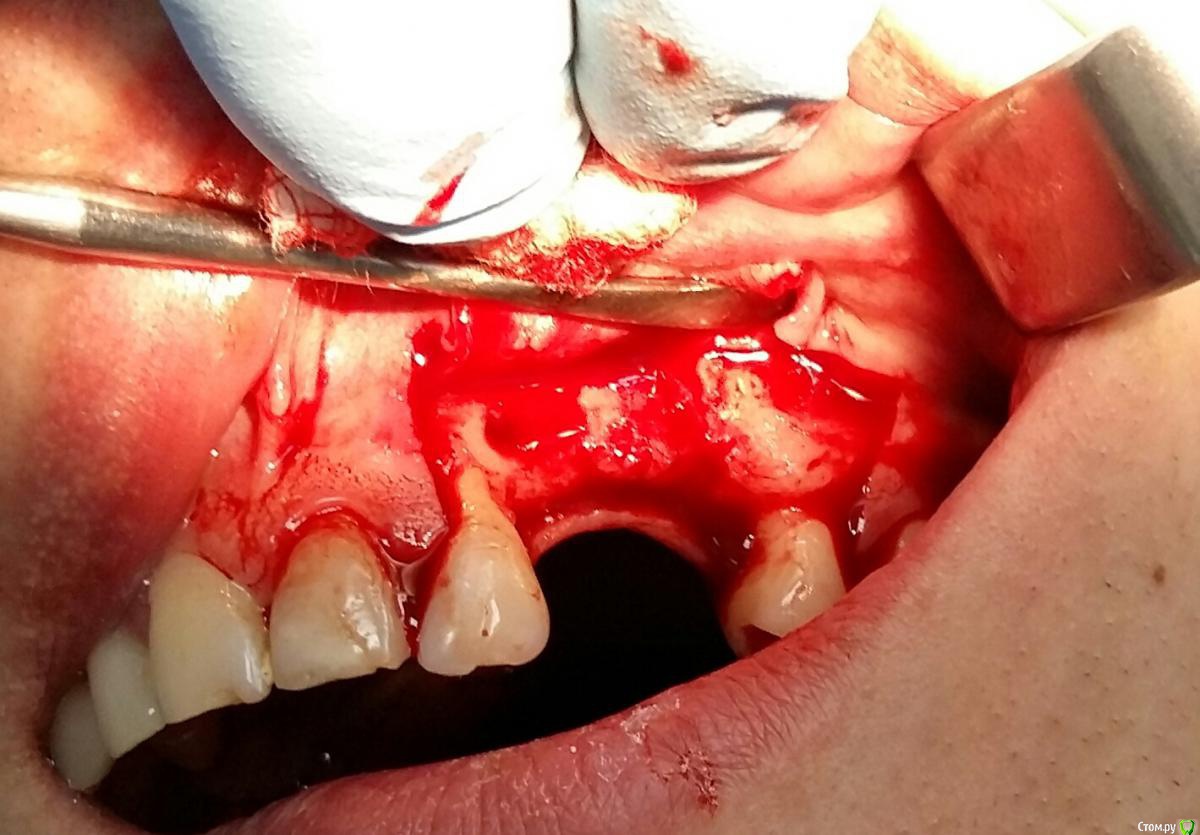

Kostoprav Опубликовано 26 марта, 2017 Поделиться Опубликовано 26 марта, 2017 (изменено) извините за качество фотографт: ауто + биопласт крошка, мембрана еволюшендырка возле 22-ревизия периапикального процесса Изменено 26 марта, 2017 пользователем Kostoprav 3 Ссылка на комментарий